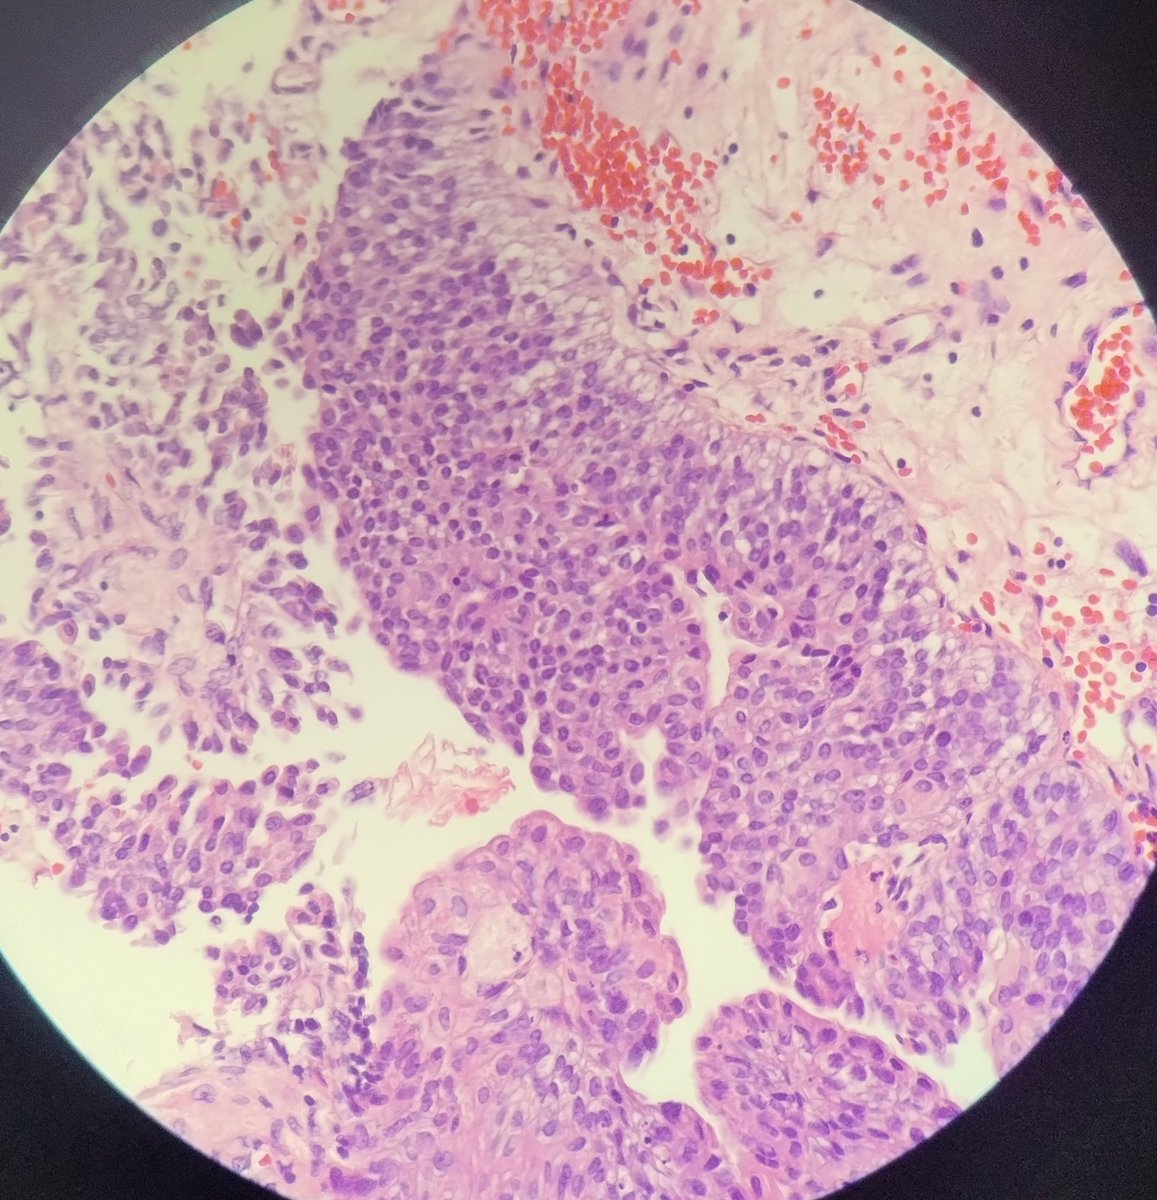

43 male , urinary bladder polypoidal mass. Is this tumor low grade papillary urothelial carcinoma . Focally I feel high grade.#pathtwitter #GUpath